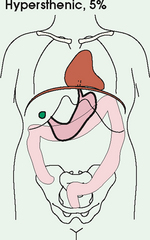

An organ such as the gallbladder may vary in position by 8 inches, depending on the body habitus. The stomach may be positioned horizontally, high, and in the center of the abdomen for one type of habitus and positioned vertically, low, and to the side of the midline in another type. Fig. 3-9 shows an example of the placement, shape, and size of the lungs, heart, and diaphragm in patients with four different body habitus types.

Fig. 3-9 Placement, shape, and size of lungs, heart, and diaphragm in patients with four different body habitus types. A, Sthenic. B, Hyposthenic. C, Asthenic. D, Hypersthenic.

Box 3-1 describes specific characteristics of the four types of body habitus and outlines their general shapes and variations. The four major types of body habitus and their approximate frequency in the population are identified as follows:

More than 85% of the population has either a sthenic or hyposthenic body habitus. The sthenic type is considered the dominant type of habitus. The relative shape of patients with a sthenic or hyposthenic body habitus and the position of their organs are referred to in clinical practice as ordinary or average. All standard radiographic positioning and exposure techniques are based on these two groups. Radiographers must become thoroughly familiar with the characteristics and organ placements of these two body types.

Radiographers must also become familiar with the two extreme habitus types: asthenic and hypersthenic. In these two small groups (15% of the population), the placement and size of the organs significantly affect positioning and the selection of exposure factors. Consequently, radiography of these patients can be challenging. Experience and professional judgment enable the radiographer to determine the correct body habitus and to judge the specific location of the organs.

Body habitus is not an indication of disease or other abnormality, and it is not determined by the body fat or physical condition of the patient. Habitus is simply a classification of the four general shapes of the trunk of the human body. When positioning patients, the radiographer should be conscious that habitus is not associated with height or weight. Four patients of equal height could have four different trunk shapes (Fig. 3-10).

Fig. 3-10 Different trunks are shown for asthenic and hypersthenic habitus, the two extremes. The abdomen is the same length in both patients (diaphragm to pubic symphysis). The abdominal organs are in completely different positions. Note high stomach in hypersthenic habitus (green color) and low stomach in asthenic habitus. (Art is based on actual autopsy findings by R. Walter Mills, MD.)